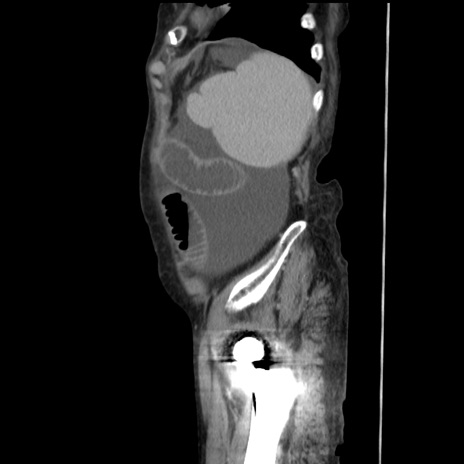

症例31(矢状断像)

【症例】80歳代 女性

【主訴】腹部膨満感

【現病歴】他院にて肝硬変にてフォロー中。1週間前から便秘、腹部膨満感、臍部腫瘤あり受診となる。

【既往歴】肝硬変

【身体所見】腹部膨隆あり、皮膚変化なし、疼痛なし。

【データ】WBC 4600、CRP 0.25